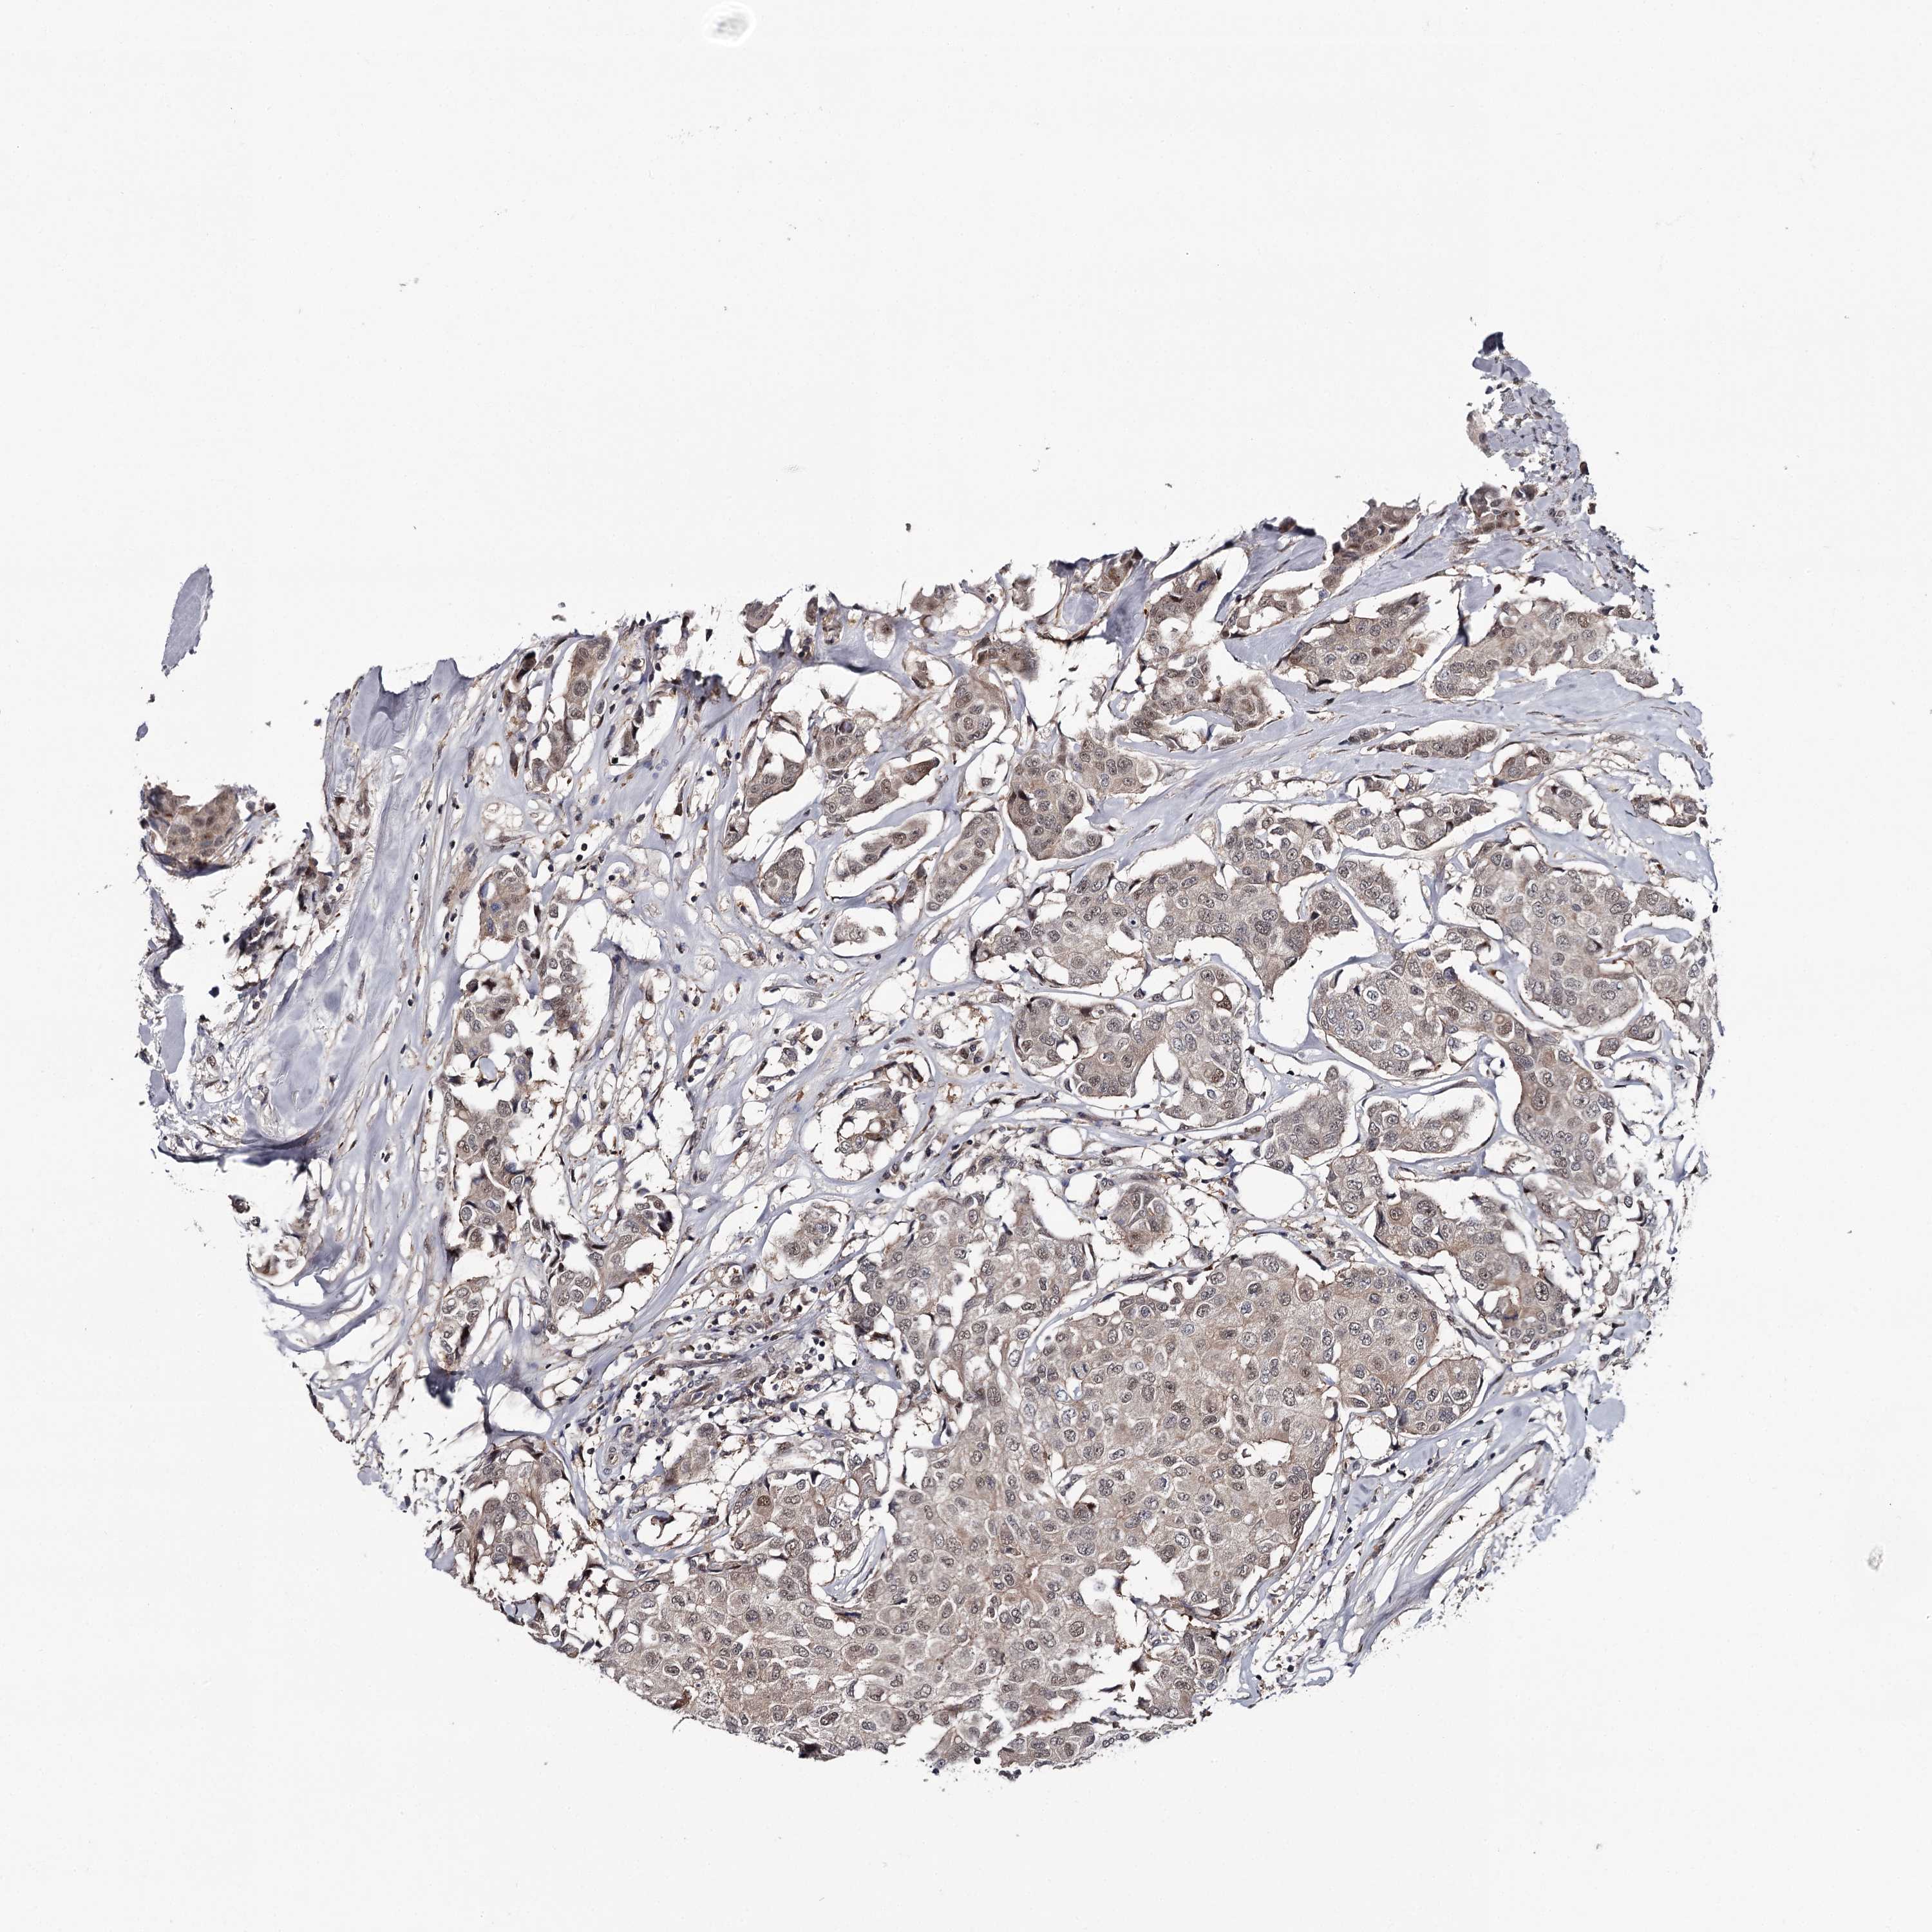

BRCA TCGA BRCA VALIDATION PROTEIN EXPRESSION

ANTIBODIES

AND

VALIDATION